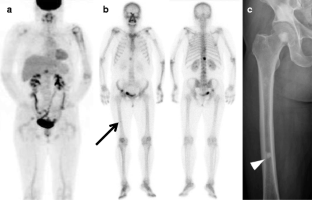

Fig. 1

Fig. 2

Fig. 3

Fig. 4

Fig. 5

Fig. 6